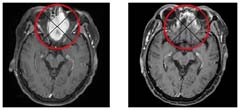

이미지

윤모씨의 눈문샘암이 재발한 비강암 CT사진(왼쪽)과 토모테라피 치료 후 암덩어리가 사라진 사진. / 신지호 헬스조선 기자 spphoto@chosun.com